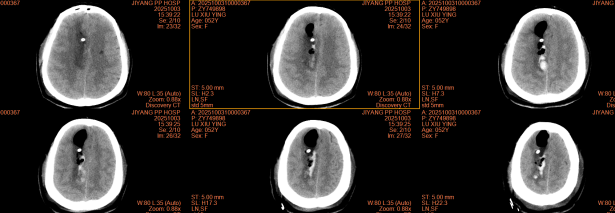

手术中,首先通过神经导航系统精准定位血肿核心位置,规划最优手术路径,误差控制在1毫米以内。随后,在可视化内镜引导下,利用吸引碎吸设备将固态血肿击碎并温和吸出,同时通过内镜实时观察血肿清除情况,避免损伤周围正常脑组织,术中出血量不足50ml,术后患者意识状态明显改善,复查CT示血肿清除率达90%以上。

术后CT ↑